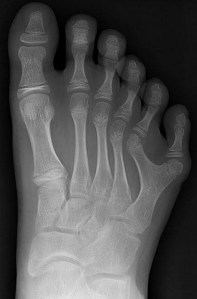

Brazilian family with six fingers and toes on hands and feet.

Subject to this 835th contact report, also with real photos attached below:

關於第835次接觸報告的主題,附有真實照片如下:

14 Members of a Family From Brazil Have Six Limbs

on Each Hand and Foot.

巴西的一個家庭有14個成員,每隻手和每隻腳都有六個指頭。

They Make the Best of It – as Piano Players or Goalkeepers.

A family with a special genetic mutation lives near the Brazilian capital Brasilia: 14 of the 23 family members have six fingers on each hand and six toes on each foot. The reason for the anatomical peculiarity in the Da Silvas is polydactyly, a rare genetic disorder. (… when earthly scientists are so stupid that they claim things from which even a complete idiot must recognise the imbecility of the whole thing …)

在巴西首都巴西利亞(Brasilia)附近,有一個家庭擁有特殊的基因突變:23個家庭成員中的14個人每隻手都有六個手指,每隻腳都有六個腳趾。這種解結構特異性是由「多指症」(polydactyly;或稱多指畸形)引起的,這是一種罕見的基因疾病。(… 如果地球科學家如此愚蠢,竟然宣稱一些連一個白癡都能辨識出其荒謬的事情 …)

In a feature on the British TV programme ‘Body Bizarre’, the Da Silvas tell how they use genetic mutation to their advantage: João Assis is an excellent goalie: “I can hold balls that would escape others. Thanks to the extra finger, I have a better grip," he says.

在英國電視節目《Body Bizarre》的一個報導中,Da Silvas家族講述了他們如何利用基因突變的優勢:João Assis是一名出色的守門員:“我可以阻止其他人無法阻擋的球。多出來的手指使我握球更好,”他說。

His cousin Maria Morena, on the other hand, is musically gifted: she plays the piano and can play more notes than anyone else with her extra finger. “My piano teacher is jealous of me because I have much more range than him," the teenager says with amusement.

另一方面,他的表妹Maria Morena在音樂方面很有天賦:她會彈鋼琴,可以用她多餘的手指比別人彈出更多的音符。憑藉額外的手指能彈奏比其他人更多的音符。這位十幾歲的少年開玩笑地說:“我的鋼琴老師嫉妒我,因為我的彈奏範圍比他大得多。”

The sixth limb on her hands and feet has become a landmark for the family, ‘Daily Mail’ reports. Family man Francisco de Asis is called ‘Mister Six'". Every time there is a pregnancy in the Da Silva family, the first question is not whether it will be a boy or a girl, but whether the child will have five or six fingers on each hand. (kle)

根據《每日郵報》(Daily Mail)的報導,她手和腳上的第六個肢體已成為這個家族的標誌。家族父親Francisco de Asis被稱為“六先生”(Mister Six)。每當Da Silva家族中有一個懷孕的時候,第一個問題不是男孩還是女孩,而是這個孩子每只手有五個還是六個手指。(kle)

This is very interesting, although it is not an anomaly, as is probably assumed by earthly scientists and called polydactyly by them. What I see here pictorially points to very distant descendants of foreigners who came to the Earth from a distant galaxy many millennia ago and mated with Earth-humans, whose descendants and again their descendants, etc., passed on physical peculiarities down to the present time, thus testifying to the immigration of foreigners to the Earth at very early times.

這非常有趣,但這不是地球科學家所認為的異常情況,也不是他們所稱之為「多指症」的異常情況。我在這裡看到的東西表明了來自遙遠外星系的後代,他們在數千年前來到地球並與地球人交配,其後代又傳承下去,一直到現代繼續傳承身體特徵,這證明了遙遠時期外星人在地球上的移民。